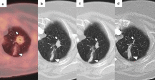

Image-guided percutaneous lung ablation has proven to be a valid treatment alternative in patients with early-stage non-small cell lung carcinoma or oligometastatic lung disease. Available ablative modalities include radiofrequency ablation, microwave ablation, and cryoablation. Currently, there are no sufficiently representative studies to determine significant differences between the results of these techniques. However, a common feature among them is their excellent tolerance with very few complications. For optimal treatment, radiologists must carefully select the patients to be treated, perform a refined ablative technique, and have a detailed knowledge of the radiological features following lung ablation. Although no randomized studies comparing image-guided percutaneous lung ablation with surgery or stereotactic radiation therapy are available, the current literature demonstrates equivalent survival rates. This review will discuss image-guided percutaneous lung ablation features, including available modalities, approved indications, possible complications, published results, and future applications.